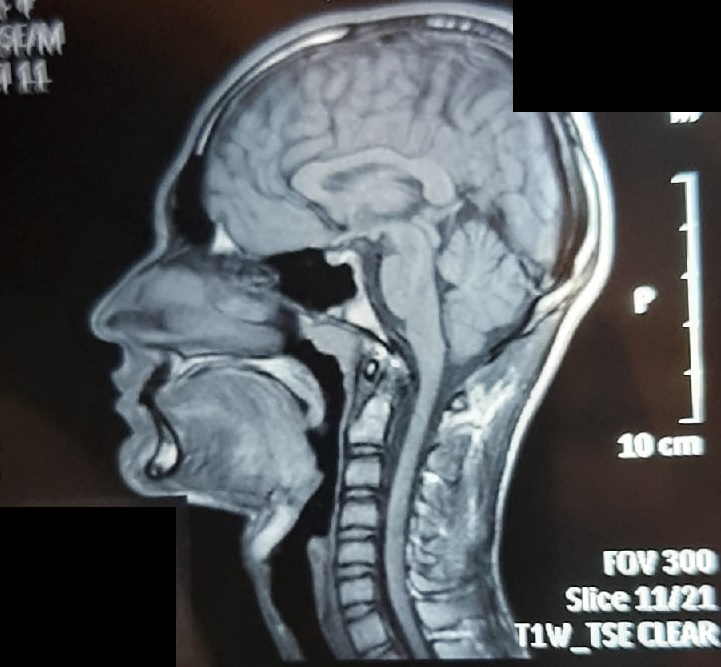

image.jpg

>>7437643

>С такой будкой я бы скинул листву лет в 14, думаю.

Если бы помимо будки всё остальное было заебок, то возможно бы скинул. А если как у меня, то нет. Вот кста мрт нашел своё